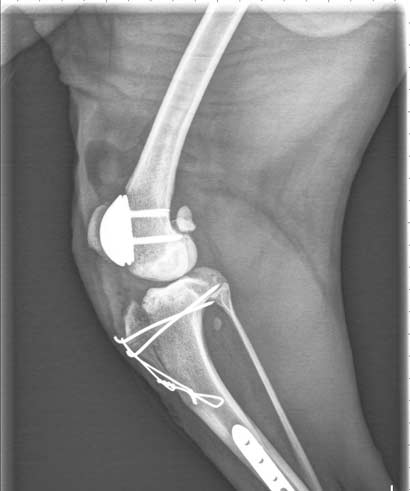

Der liebe Max hat seine erste Operation gut überstanden!!! Nach einer mehrstündigen sehr komplizierten Operation ist er nun stolzer Besitzer einer Kniescheibengelenksendprothese. Außerdem wurde eine Achsenkorrektur vorgenommen, so dass sein Bein jetzt wieder absolut gerade steht. Der tapfere Max wird nun rund um die Uhr sehr liebevoll von seiner Pflegefamilie umsorgt. Er benötigt nun -bevor die OP des zweiten Beines ansteht- noch mehrere Wochen strikte Erholung, darf sich möglichst wenig bewegen, nicht spielen, nicht hüpfen, nicht rennen.

Niederschmetternde Untersuchungsergebnisse bei dem lieben Border Collie Rüden Max :-(((

Nachdem weiterführende Untersuchungen durchgeführt wurden, unter anderem auch ein CT, ergaben sich leider sehr traurige Ergebnisse. Bei dem armen Max sind beide Knie total kaputt, was sich leider auch schon auf den Rest der Beine ausgewirkt, und zu einer kompletten "Achsverschiebung" geführt hat :-(

An dem einen Bein hat er sogar schon eine beginnende Schiefstellung der Pfote :-(((

Ist es nicht schon schlimm und unfassbar genug, dass der arme Bub schon viel zu lange mit diesen Knien und den Schmerzen leben mußte, so war die Besprechung mit den behandelten Ärzten unfassbar und niederschmetternd! Das unfassbar traurige ist, dass Max ohne ärztliche Hilfe leider nicht mehr viel Zeit bleibt in welcher er seine Hinterläufe gebrauchen, sprich bewegen kann..... Die Ärzte erklärten uns, dass selbst eine sehr aufwendige Operation der Knie und einer Ausrichtung der Knochen leider nicht zu einem zufriedenstellenden Erfolg führen würden, da die Knie schon zu stark verformt und kaputt sind.

Jetzt bleibt für den lieben Max nur eine einzige Chance:

Er braucht künstliche Knie!

Ihm geht es den Umständen entsprechend gut. Die mehrstündige OP verlief zufriedenstellend und die Prothese konnte eingesetzt werden. Momentan kann Max sein Bein noch nicht belasten und auch die Reflexe an dem operierten Bein sind noch nicht ganz wieder da, aber das kommt mit der Zeit wieder. Jetzt heißt es erst mal viel schlafen, fressen und getragen werden. Alle paar Stunden wird Max nun rausgetragen, um sich zu erleichtern, da er aufgrund der Infusionen sonst seine Blase noch nicht ganz im Griff hat. In wenigen Tagen kann Max sein Bein dann leicht belasten, darf aber für die nächsten Wochen noch so gut wie nicht laufen, damit die Prothese gut verwachsen kann. Max ist ein ganz tapferer Patient, der (bis jetzt ;) ) von sich aus Wert auf Ruhe legt, aber auch schon ordentlich Appetit hat und schon seine ganze Portion Futter gefressen hat. Auch seine Medikamente wird er vermutlich ohne Probleme fressen, da er einfach alles lecker findet. Nächste Woche geht er zur Kontrolle nochmal in die Klinik und in zwei Wochen werden die Fäden gezogen. Solange trägt er natürlich einen Kragen, damit die Wunde gut heilen kann. In circa vier Wochen geht es dann erst mal ins Röntgen, um zu schauen, wie sich das Bein entwickelt.

Sein zweites Kniegelenk wird in einer weiteren mehrstündigen Operation ersetzt.